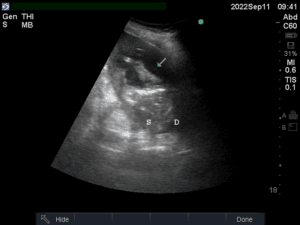

Venous excess Doppler ultrasound (VExUS) grading system

The VExUS grading system is calculated following the steps of the original paper. First the IVC is measured and, if bigger than 20 mm, the portal, hepatic and intrarenal veins are scanned. Doppler interrogation of these vessels yields a specific pattern corresponding to a level of venous congestion: normal, mild, or severe. According to the results, the VExUS score is obtained as follows: VEXUS 0: IVC < 20mm; VEXUS 1: IVC ≥ 20mm with normal patterns or mild abnormalities; VEXUS 2: IVC ≥ 20mm with severe abnormality in at least one pattern and VEXUS 3: IVC ≥ 20mm and severe abnormalities in multiple patterns.

Considering the technical difficulties in achieving the best ultrasound images for this protocol, the authors allow the use of the best window and view consider by the operator.